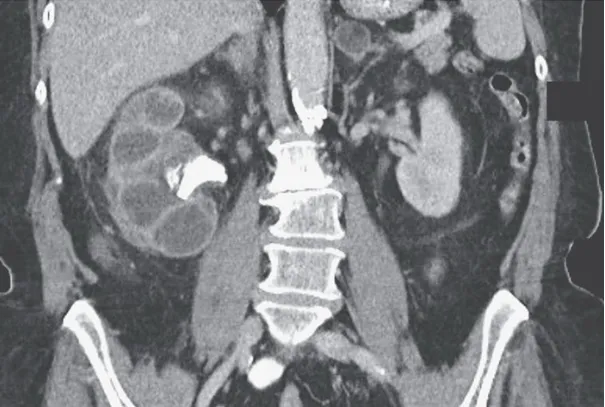

A tomografia computadorizada de abdome revelou um rim direito aumentado, com a presença de um cálculo coraliforme na junção ureteropélvica, atrofia cortical e dilatação do cálice, uma aparência referida como o "sinal da pata de urso."

Foi iniciado tratamento com antibióticos intravenosos e realizada uma nefrostomia percutânea. A cultura da drenagem identificou o crescimento de Proteus mirabilis. Após avaliação com cintilografia, foi identificada a ausência de função renal no rim direito, levando à realização de uma nefrectomia.

Foi feito o diagnóstico de pielonefrite xantogranulomatosa.